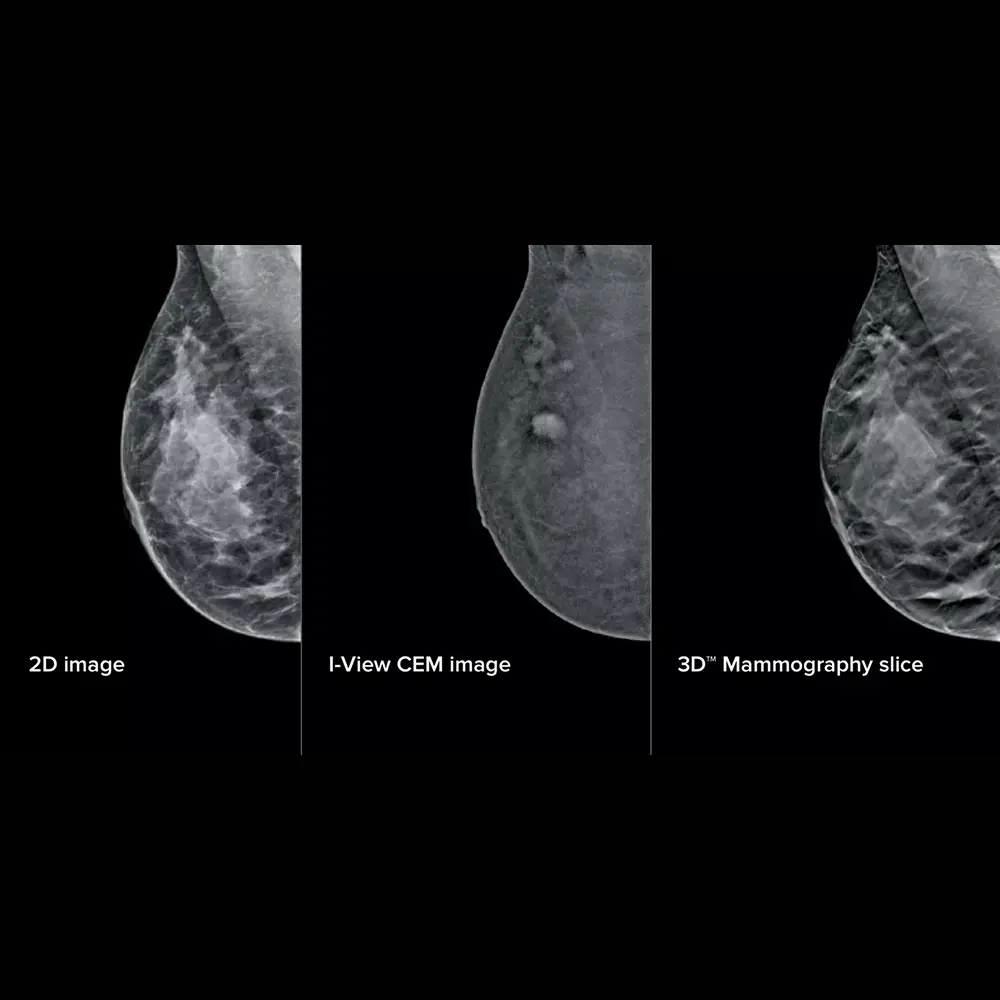

I-View è il software avanzato di Hologic per l’imaging mammografico con mezzo di contrasto, basato su tecnologia 2D a doppia energia (CE2D). Progettato per rendere visibili lesioni non identificabili con la mammografia tradizionale, I-View permette una valutazione più chiara e accurata della morfologia e vascolarizzazione di eventuali anomalie sospette.

Il principio alla base della mammografia con contrasto è l’aumento del flusso sanguigno in corrispondenza di aree tumorali. Dopo l’iniezione endovenosa di un mezzo di contrasto iodato, vengono acquisite immagini mammografiche ad alta e bassa energia. Il software I-View elabora queste immagini sottraendo i dati strutturali del tessuto mammario per mettere in risalto le aree di maggiore assorbimento, rivelando la presenza di potenziali lesioni maligne.